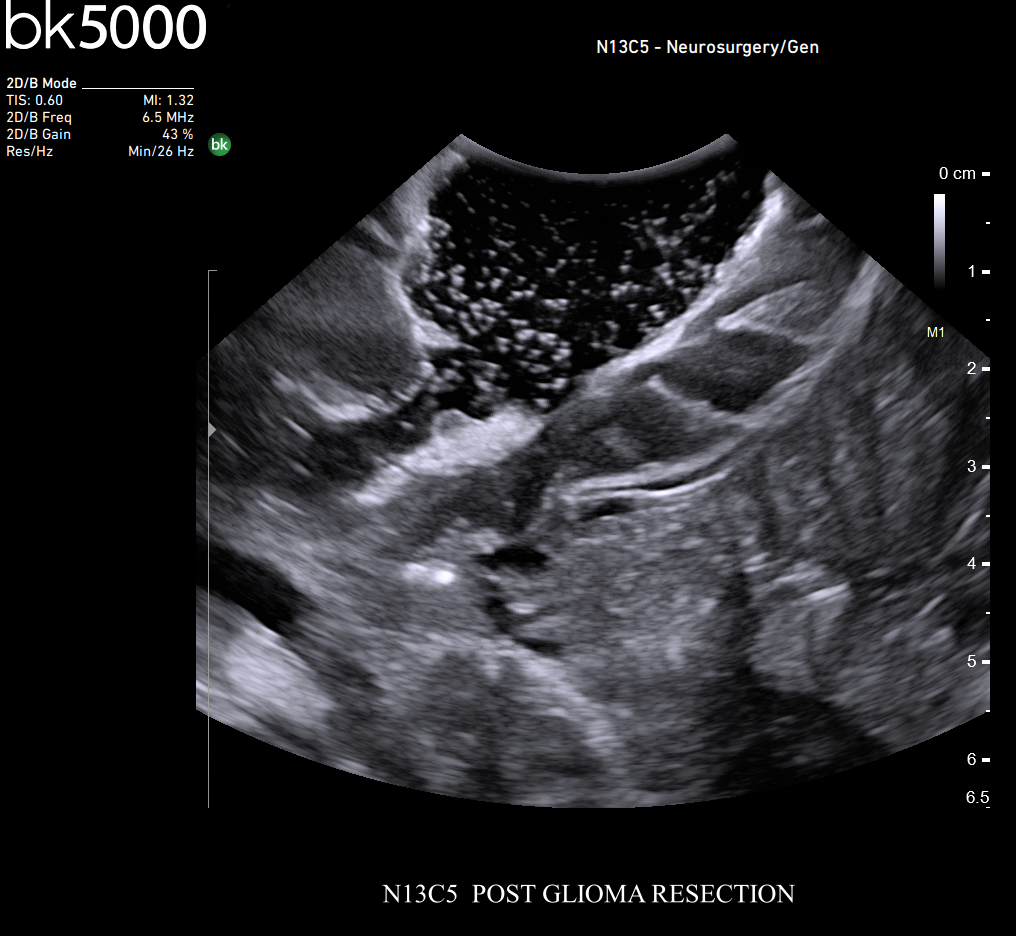

Ultrasound can improve neurosurgical procedures by helping you navigate and identify lesions and anatomical structures in real-time. This is particularly important as the data obtained from a preoperative CT or MRI scan can be outdated at the time of surgery. The bk5000 neurosurgical system provides the highest quality images that allow you to clearly see the margins of a lesion and to determine the best course of action. Using advanced graphics processing technology, this powerful system provides immediate, auto-optimized images that allow you to see the information you need, faster.

Transducers designed for Neurosurgery

The specialized, high-resolution, sterilizable neurosurgery transducers enable you to obtain detailed images of the brain and spinal cord. They have a convenient Smart™ button that lets you activate the transducer, then freeze, store or print the images at the press of a button. Disposable, easy-to-use needle guides assist with targeting lesions.